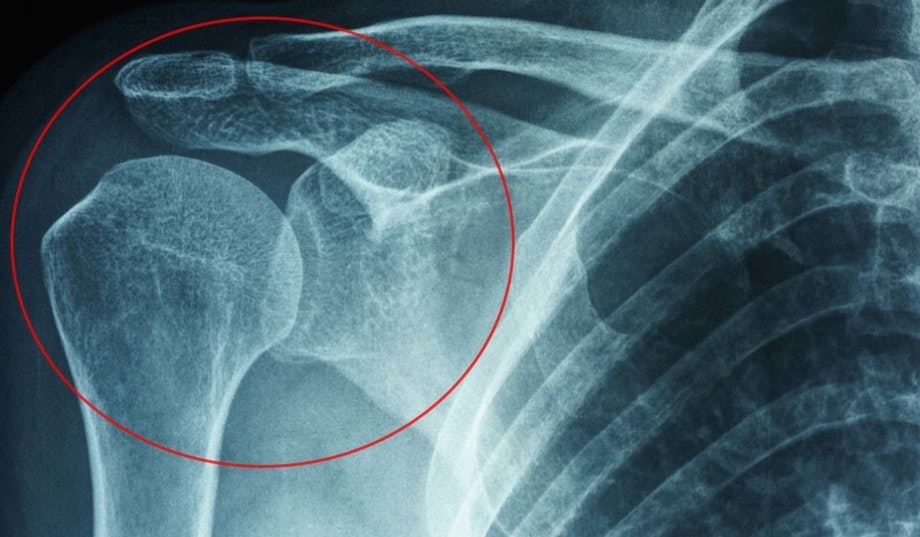

Jäätynyt olkapää röntgenkuvassa

JÄÄTYNYT OLKAPÄÄ Olkaluun ja ­lapaluun välistä olkaniveltä ympäröi sidekudoksesta koostuva nivelkapseli. Jäätynyt olkapää on tila, jossa kapseli paksuuntuu ja kiristyy ja siihen syntyy tulehduksen kaltainen tila. Tällöin nivelkapselin sidekudos jäykistyy.

Olkaluun ja ­lapaluun välistä olkaniveltä ympäröi sidekudoksesta koostuva nivelkapseli. Jäätynyt olkapää on tila, jossa kapseli paksuuntuu ja kiristyy ja siihen syntyy tulehduksen kaltainen tila. Nivelkapselin sidekudos jäykistyy ja kapseliin syntyy ylimääräistä kudosta, mikä estää niveltä voitelevan nesteen syntymistä. Nivelen liikkuvuus heikkenee merkittävästi, ja vaiva aiheuttaa kovia kipuja.